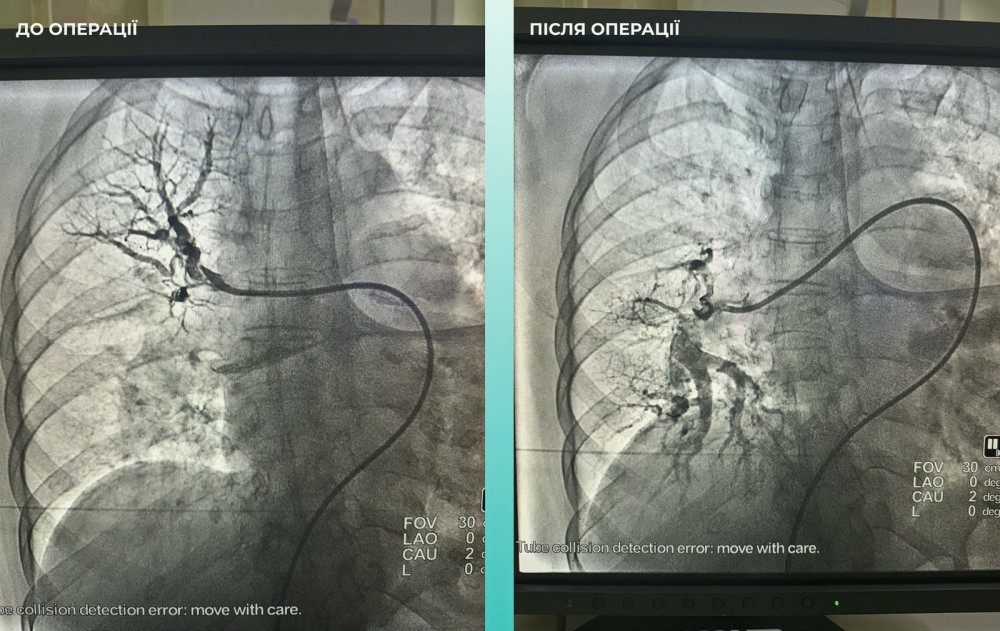

Крім того, лікарі зауважили, що у пацієнтки виникли проблеми з диханням, тому додатково провели обстеження легень. Виявилося, що у неї була тромбоемболія легеневої артерії.

Команда лікарів вирішила провести одночасну тромбектомію на обох артеріях, що було вкрай необхідно для порятунку життя.

Операція завершилася успіхом, і пацієнтка почувається значно краще: вона в свідомості і може рухати кінцівками.